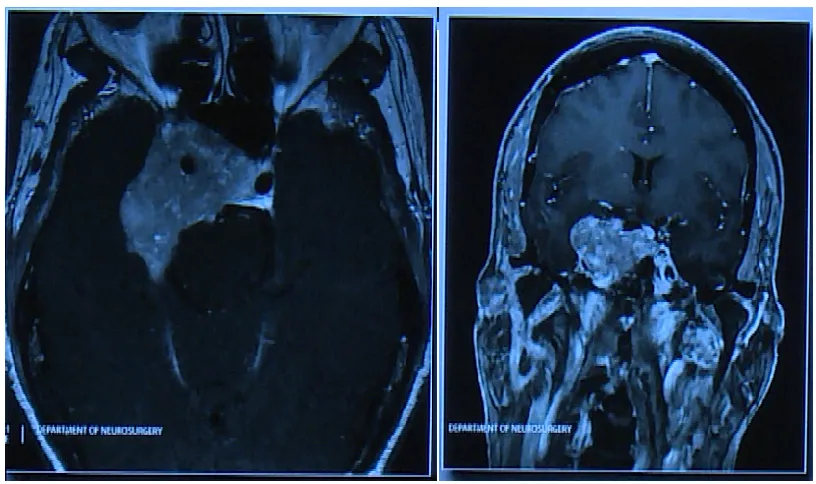

巨大垂体瘤案例分享 一位62岁女性患者,与垂体瘤抗争长达35年,曾因垂体瘤复发接受放射治疗。此次因出现复视症状随访,发现已经发展巨大的垂体瘤。 进行开颅手术,术后影像片子显示肿瘤...